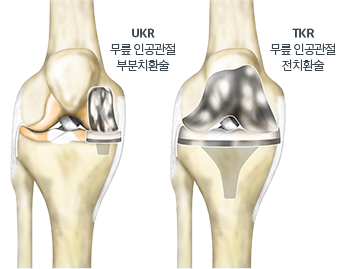

무릎 인공관절 수술은 많은 사람들이 고통받고 있는 관절 질환을 효과적으로 치료하는 방법 중 하나입니다. 이 수술을 통해 많은 환자들이 통증에서 벗어나 보다 나은 삶의 질을 누릴 수 있게 됩니다. 하지만, 수술 후 회복 과정은 개인마다 매우 다를 수 있으며, 회복 기간 동안 환자는 신체적, 정서적, 사회적 변화에 직면하게 됩니다. 이 블로그 포스트에서는 무릎 인공관절 수술 이후의 회복 기간을 단계별로 나누어 자세히 설명하고, 각 단계에서 어떤 점을 유의해야 하는지 알아보겠습니다. 따라서, 무릎 인공관절 수술을 고려하는 분들이라면 이 글이 큰 도움이 될 것입니다. 궁금한 점이 있거나 추가 정보가 필요하다면 아래의 버튼을 클릭해 주세요.